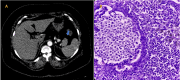

Figure 1

Figure 1. (A) Contrast-enhanced CT scan image of the abdomen in the arterial phase shows a mildly enhancing solid mass in the head of the pancreas encasing the celiac trunk, splenic artery, and common hepatic artery (precontrast HU-47, postcontrast HU-65). (B) Microscopic section of the pancreas shows infiltrating well- to poorly formed glandular/ductal structures surrounded by remarkably desmoplastic stroma (H&E stain, original magnification 10×). It was conformed to be a case of adenocarcinoma of the head of the pancreas

CT: computed tomography; H&E: hematoxylin and eosin; HU: Hounsfield units